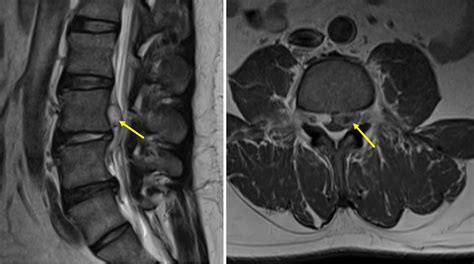

First, they’ll examine the discs themselves. They’ll check for any loss of disc height (a sign of degeneration), dehydration within the disc (which appears darker on certain MRI sequences), and the integrity of the annulus fibrosus. They’re specifically hunting for that tell-tale sign of a sequestered fragment – a piece of disc material that has visibly broken off from the main disc and is now lying outside the normal disc space, often within the spinal canal or a neural foramen (the opening where a nerve root exits the spine).

Crucially, they’ll be assessing the relationship of this fragment to the surrounding structures, particularly the nerve roots and the spinal cord. They’ll be looking for signs of compression, displacement, or inflammation of these neural elements. The sequestered disc MRI will show them how severely these nerves are being affected. A large fragment or a fragment in a critical location might be shown to be significantly pinching a nerve, while a smaller fragment might be causing less apparent pressure.

They’ll also note the exact location – is it in the lumbar spine (lower back), cervical spine (neck), or thoracic spine (mid-back)? Which nerve root is potentially being affected? Is the fragment extruded (pushed out but still attached) or truly sequestered (completely detached)? These details are absolutely critical for determining the best treatment approach.